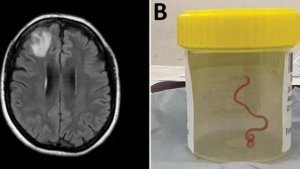

Australia: Bwa mbere ku isi inzoka nzima bayisanze mu bwonko bw’umugore

Ku nshuro ya mbere ku isi, abahanga muri siyanse baravuga ko inzoka ya 8cm bayisanze ari nzima (…)